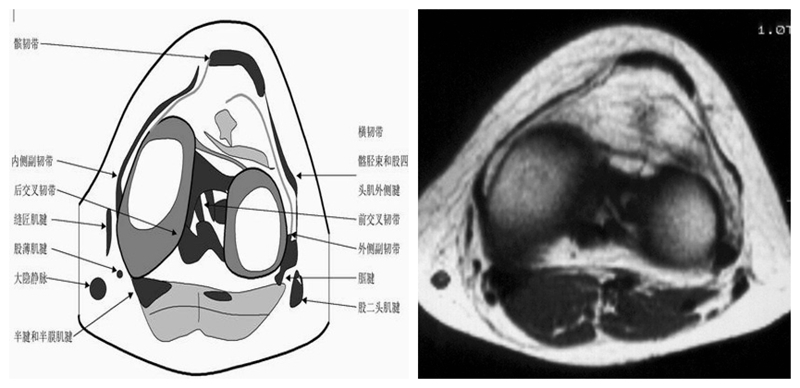

膝关节横断面MRI解剖

三维影像首选的方位,便于与CT比较,可准确地展现髌骨内外侧关节面。

横断面解剖第一层